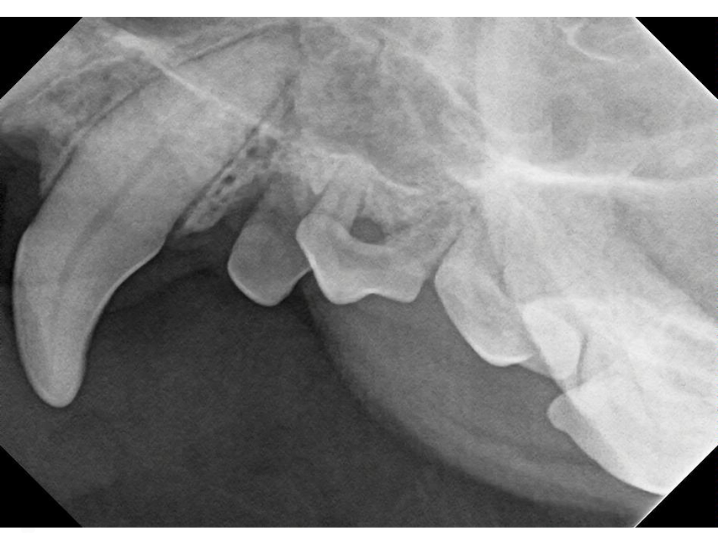

Digital Dental Radiology

Insight into underlying issues.